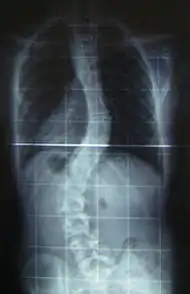

Scoliosis is a medical condition in which a person's spine has a sideways curve.[2] The curve is usually "S"- or "C"-shaped over three dimensions.[2][7] In some, the degree of curve is stable, while in others, it increases over time.[3] Mild scoliosis does not typically cause problems, but more severe cases can affect breathing and movement.[3][8] Pain is usually present in adults, and can worsen with age.[9]

When scoliosis is suspected, weight-bearing, full-spine AP/coronal (front-back view) and lateral/sagittal (side view) X-rays are usually taken to assess the scoliosis curves and the kyphosis and lordosis, as these can also be affected in individuals with scoliosis. Full-length standing spine X-rays are the standard method for evaluating the severity and progression of scoliosis, and whether it is congenital or idiopathic in nature. In growing individuals, serial radiographs are obtained at 3- to 12-month intervals to follow curve progression, and, in some instances, MRI investigation is warranted to look at the spinal cord.[49]

The standard method for assessing the curvature quantitatively is measuring the Cobb angle, which is the angle between two lines, drawn perpendicular to the upper endplate of the uppermost vertebra involved and the lower endplate of the lowest vertebra involved. For people with two curves, Cobb angles are followed for both curves. In some people, lateral-bending X-rays are obtained to assess the flexibility of the curves or the primary and compensatory curves.